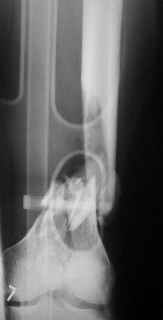

And why LISS is superior here than nail?

Look what we would have done.